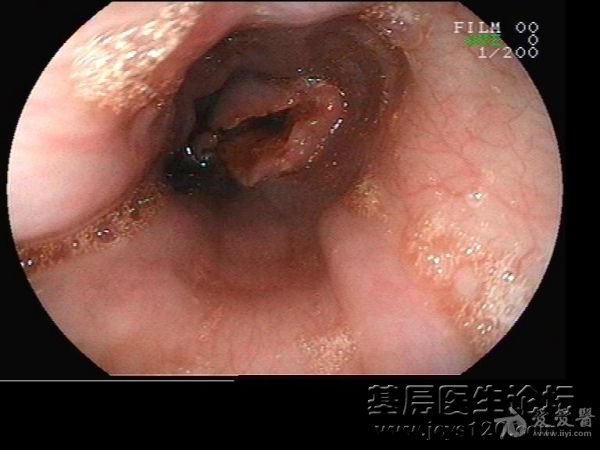

• 这样的食道我第一次看到 attach_img agree

• wodejune 2012-8-23

• 一个35岁吞咽困难,反复呕吐的男性, 我帮他今天做了无痛胃镜, 食管进镜30cm好似有肿物,进境受阻,还流血,我不敢进了。要他去上级医院。 我是个胃镜新手 向给位胃镜老师、前辈求救。 胃镜操作我i ...  阅读全文>